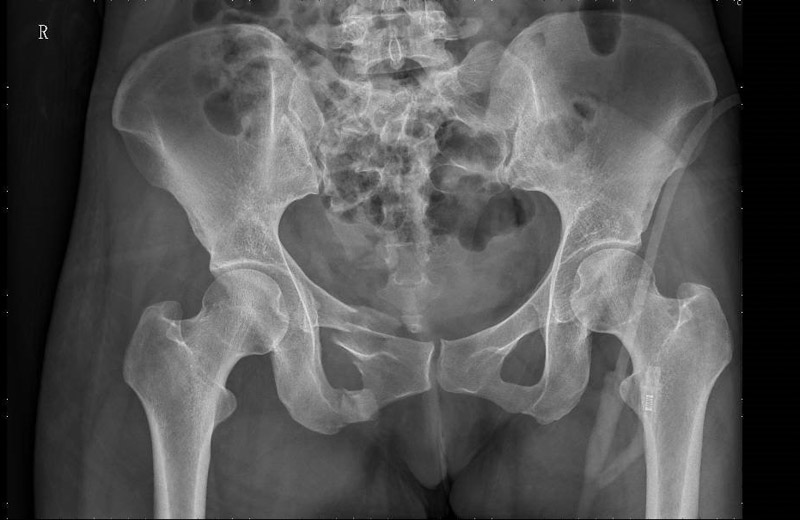

患者周女士在走路时不慎被车撞伤,被120送至当地医院,清醒后感觉臀部剧痛难忍,双髋活动受限,为求进一步治疗,转入了柳州市人民医院创伤骨科,经CT检查,患者为骨盆骨折,需手术治疗。

骨盆位置深,内部脏器结构丰富,血管神经复杂,一旦发生损伤,常常导致相应的血管神经损伤和大出血,所以骨盆骨折手术一直被认为是创伤骨科中最复杂的手术之一。且传统切开复位内固定手术对患者伤害较大,容易造成术中血管神经的损伤、术后感染等并发症的发生。

术中,创伤骨科团队将示踪器安装在患者手术处,与移动C型臂X光机相配合,手术团队根据生成图像模拟置钉,通过独有算法计算出入钉点及钉道,按照术中规划,施术者借助导向套筒,为患者精准的植入三枚螺钉,手术切口仅三个1厘米小洞,术中出血不到10毫升。